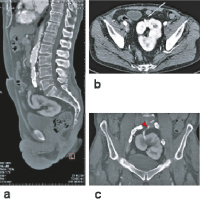

Abbildung 5a-c: CT-Angiographie. (a): Sagittale Schnittebene mit Darstellung der ventralen Ausrichtung des Hilus; (b): axiale Schnittebene mit Visualisierung beider Äste der Nierenarterie (weißer Pfeil); (c): koronare Schnittebene mit Darstellung einer Nierenarterie (roter Pfeil) und der lobulierten Oberfläche der Kuchenniere.